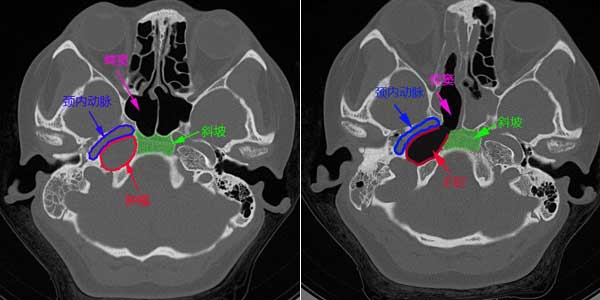

为了查清病因,邱主任给患者安排了头部CT检查,结果发现小陈右侧颅底的岩骨部有一大小为22.3mm×19.7mm类圆形影,该占位性病变位于颈内动脉的后外方,并且其与颈内动脉之间已无骨质间隔。影像科医生诊断为胆固醇肉芽肿。

颅底区域狭小,解剖复杂,特别是颈内动脉弯曲行走,如损伤后将会导致50%患者死亡,近50% 患者全身偏瘫,这决定了颅底手术的高难度和高风险。虽然邱前辉主任擅长鼻内镜颅底微创手术,其颅底手术的难度和病例数都在省内领先。但由于该病变位于颈内动脉的后外方,因此鼻内镜下切除该肿瘤的最大难题是如何绕开这个“拦路虎”。邱主任通过仔细分析和研究,决定充分利用人体如鼻腔、鼻窦的自然通道,采用鼻内镜下通过鼻腔、蝶窦,磨除蝶窦后面的部分斜坡骨质的手术路径,绕至颈内动脉后下方切除病灶。

术前影像学 术后影像学